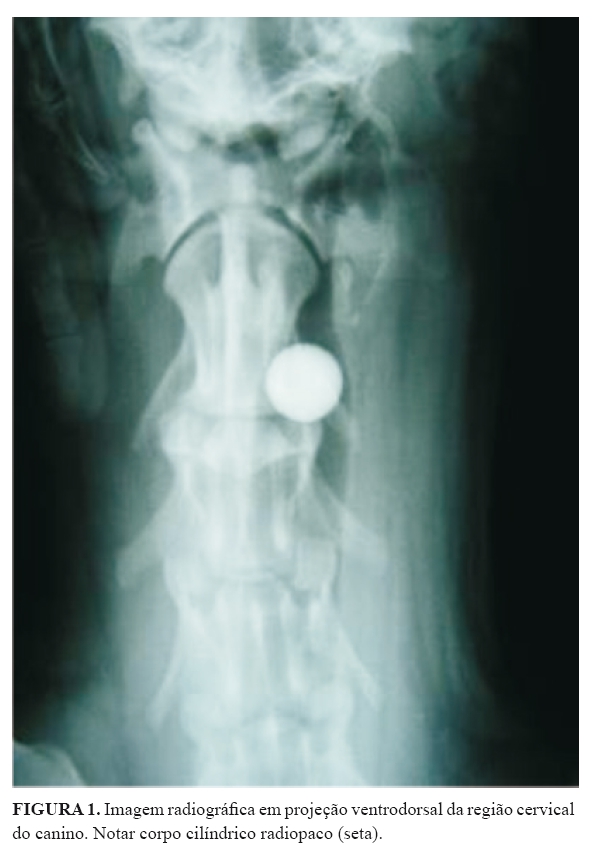

Foi atendida no Hospital Veterinário da Universidade de Cuiabá (UNIC) uma cadela da raça Rottweiler, com um ano e sete meses de idade, trazida à consulta por apresentar síncope e cianose após ingestão de ração comercial. Ao exame físico constataram-se dispneia, tosse improdutiva e cianose na mucosa oral. O animal foi submetido à terapia sintomática e a exames radiográficos após internamento. Ao ser posicionado para avaliação radiográfica do tórax, o animal demonstrou piora da dispneia. O exame radiológico revelou, nas projeções lateral e dorsoventral (Figura 1), uma estrutura radiopaca que, em ambas as projeções, apresentava formato circular com, aproximadamente, dois centímetros de diâmetro, localizado posteriormente à carina. Realizou-se esofagograma (Figura 2) para avaliação do trânsito esofágico, não sendo observada obstrução, porém o corpo estranho torácico não foi mais visualizado nesta radiografia. Sequencialmente, realizaram-se exames radiográficos do abdome e nenhuma alteração ou corpo estranho foi notado. O paciente permanecia com tosse e disfagia, sem, contudo, ter apresentado, novamente, cianose e/ou síncope. Solicitaram-se novos exames radiográficos das regiões torácica e abdominal, buscando-se encontrar o corpo estranho, e não foi revelada nenhuma alteração digna de nota. Então, realizou-se radiografia da região cervical cranial, a qual demonstrou presença de corpo estranho radiopaco na luz traqueal, que nas projeções lateral e dorsoventral apresentava formato circular (Figura 3). Foi instituída terapia paliativa com a administração de cloranfenicola (50mg/kg), pela via oral, a cada oito horas, e flunixin-meglumineb (1,0 mg/kg), pela via subcutânea, a cada 24 horas. Durante a internação, o cão apresentava-se com apetite, mas com disfagia.

O diagnóstico de corpo estranho traqueal radiopaco pode ser confirmado por meio de exame radiográfico simples (FINGLAND, 1996; NELSON, 1998), como demonstrado no caso relatado, de encontro de um corpo estranho radiopaco localizado na traqueia cervical, no caso uma bola de gude. Porém, esse corpo estranho apresentava-se móvel, deslocando-se pela traqueia e brônquios durante a respiração, o que exigiu repetições de tomadas radiográficas, a fim de se localizar precisamente a bola de gude.

O exame radiográfico no diagnóstico e localização de corpo estranho traqueal radiopaco, em região cervical de cães, é decisivo e a traqueotomia é uma técnica cirúrgica eficiente na remoção deste.